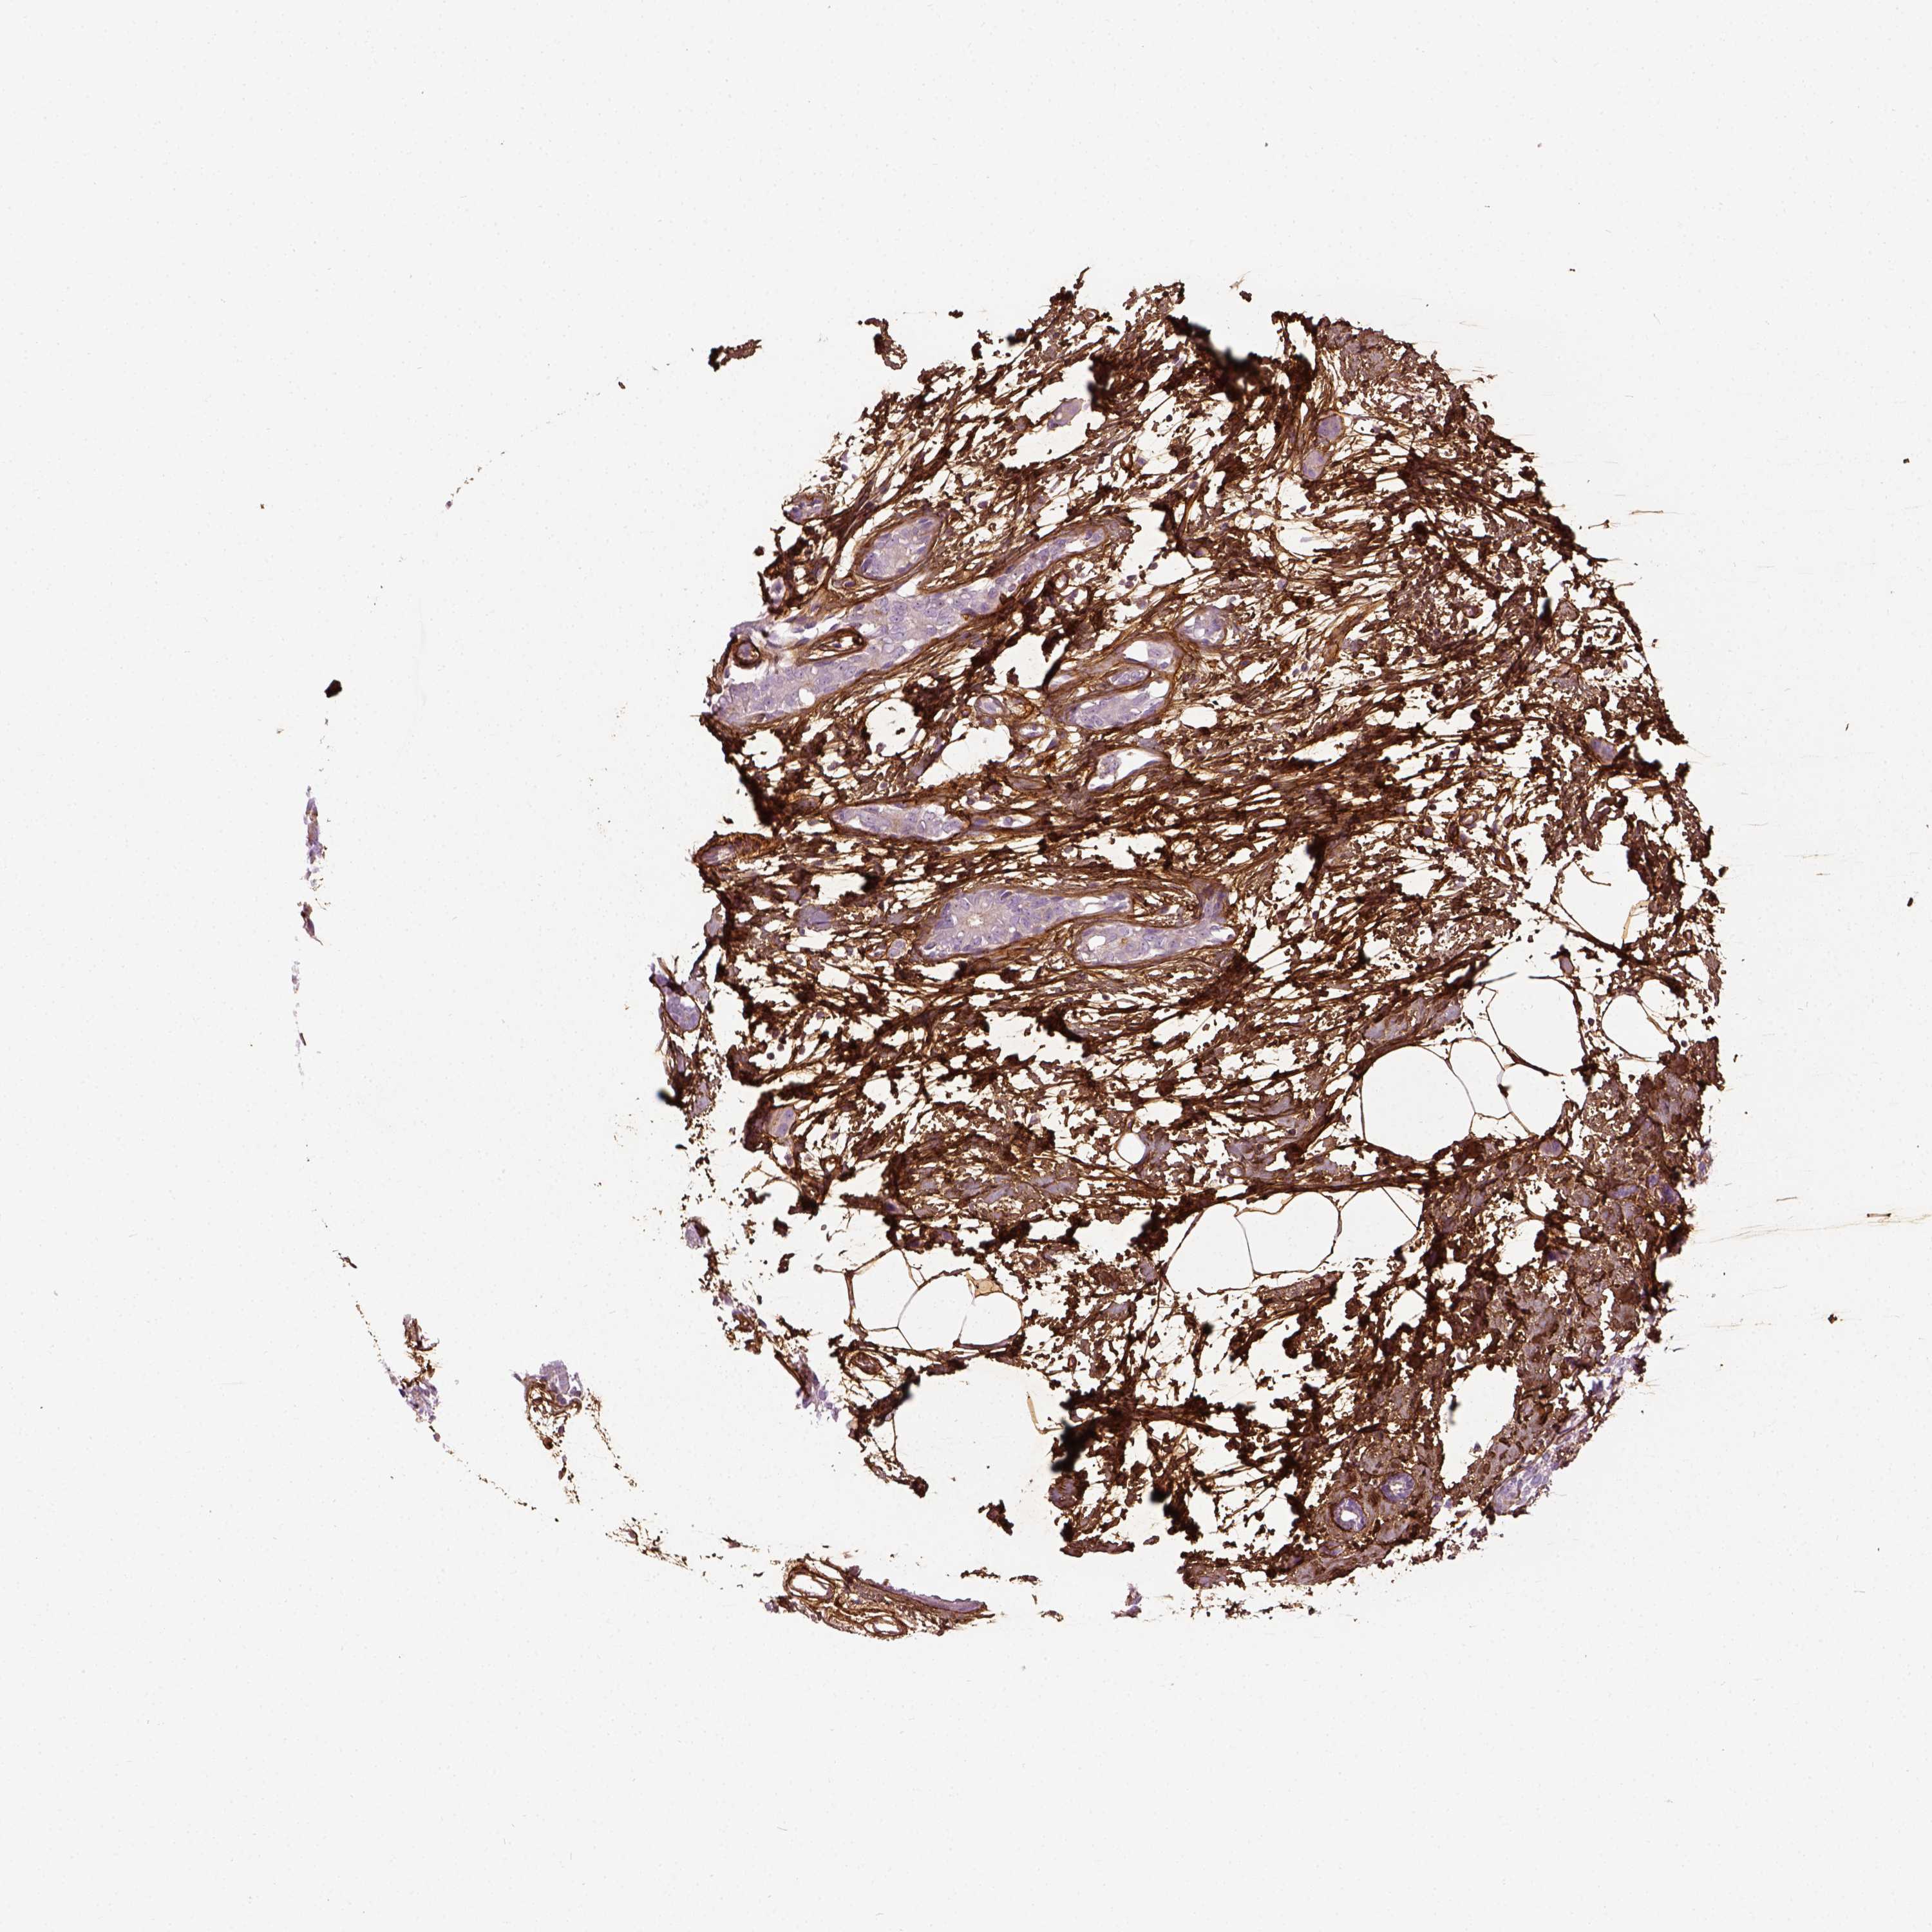

BRCA TCGA BRCA VALIDATION PROTEIN EXPRESSION